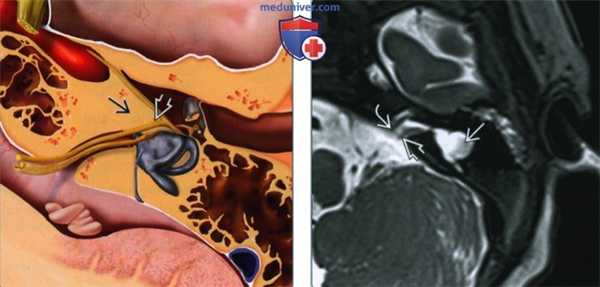

(Слева) На рисунке в аксиальной плоскости показана аплазия лабиринта. Обратите внимание на полное отсутствие всех структур внутреннего уха за исключением небольшого ВСК, содержащего только ЧН VII. Латеральная стенка внутреннего уха (мыс) уплощена.

(Справа) При аксиальной КТ в костном окне у девушки 21 года с НСТУ определяется выраженная гипоплазия костной слуховой капсулы. В области мыса видны ячейки, содержащие газ (ожидаемая локализация). Структуры внутреннего уха отсутствуют. Визуализируется канал ЧН VII с расширенным верхним коленом. Обратите внимание на гипоплазию вершины пирамиды с уменьшением ее ширины.

(Слева) При аксиальной КТ в костном окне у этой же пациентки на более краниальном уровне определяется гипоплазия костной слуховой капсулы. Визуализируется переднее колено и проксимальный тимпанический сегмент аномального канала ЧH VII.

(Справа) При корональной КТ в костном окне у этого же пациента определяется полное отсутствие структур внутреннего уха и выраженная гипоплазия костной слуховой капсулы и вершины пирамиды. Обратите внимание на отсутствие патологических изменений среднего уха и слуховых косточек, несмотря на тотальную аплазию внутреннего уха.